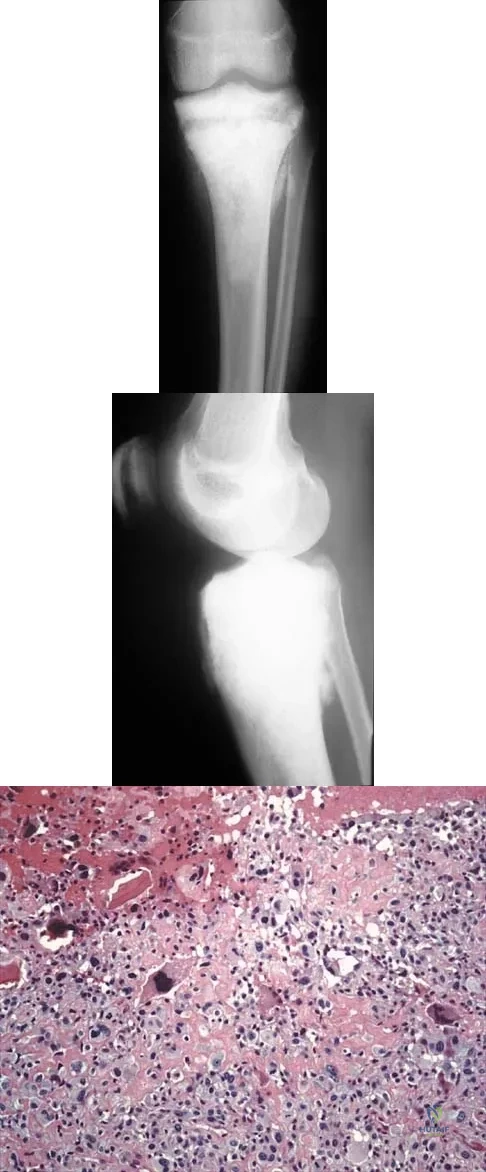

Figures 19a and 19b show the AP and lateral radiographs of an 18-year-old man who has had knee pain for 3 months. Figure 19c shows a histopathologic photomicrograph of the biopsy specimen. Which of the following factors is most likely to affect his survival?

Explanation